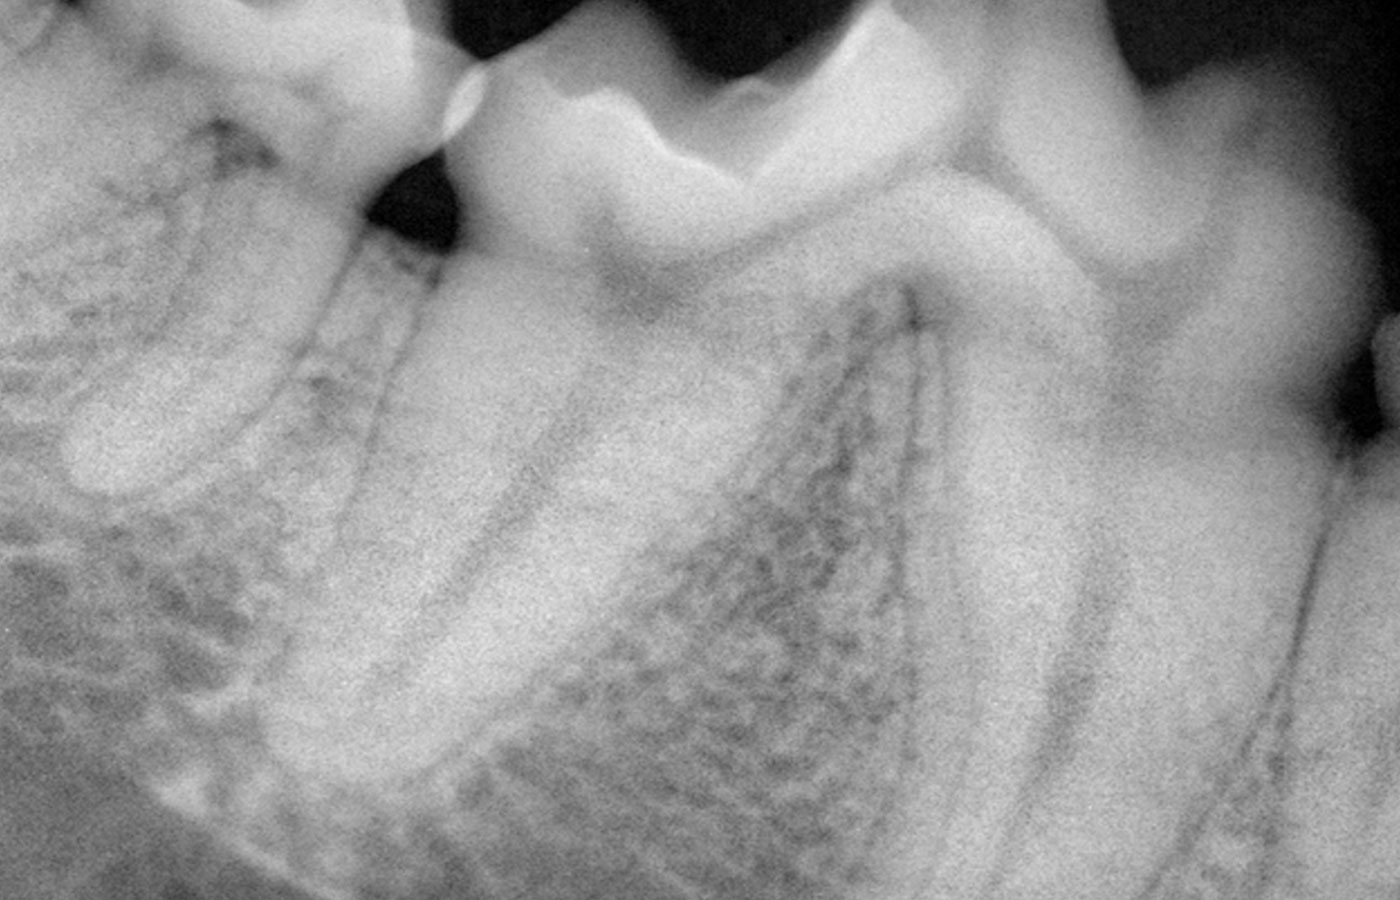

We have a complement of 4 scopes for medical and diagnostic procedures. Imaging – X-rays and contrast radiology are important diagnostic tools. We use both a standard X-ray machine and a dental-specific X-ray machine. The addition of a new Siemens G50 color Doppler ultrasound unit greatly complements and enhances the imaging of tissues, heart and abdominal organs.

Dental health is extremely important to pets. Periodontal disease is known to be a source of many kidney and heart problems.

Pets need regular dental cleanings and treatment to minimize or prevent advancing periodontal disease. Tallmadge Animal Hospital has an excellent dental facility for both general dentistry and endodontic procedures. The use of digital dental X-rays is a great asset for radiographing pets’ teeth to properly evaluate the extent of disease and plan for the most appropriate treatment.

Digital radiographs produce excellent images in much less time and better allow for root canal procedures. Root canals are performed using a “Light Speed” endodontic system. Besides regular cleanings, pets need home dental care to help slow or prevent advancing periodontal disease and tooth loss. We will happily educate you on how to take care of your pet's teeth! Cats are at particular risk for odontoclastic resorptive lesions (neck lesions) that destroy the tooth at the gum line or the roots. Pets are routinely X-rayed during dental procedures.